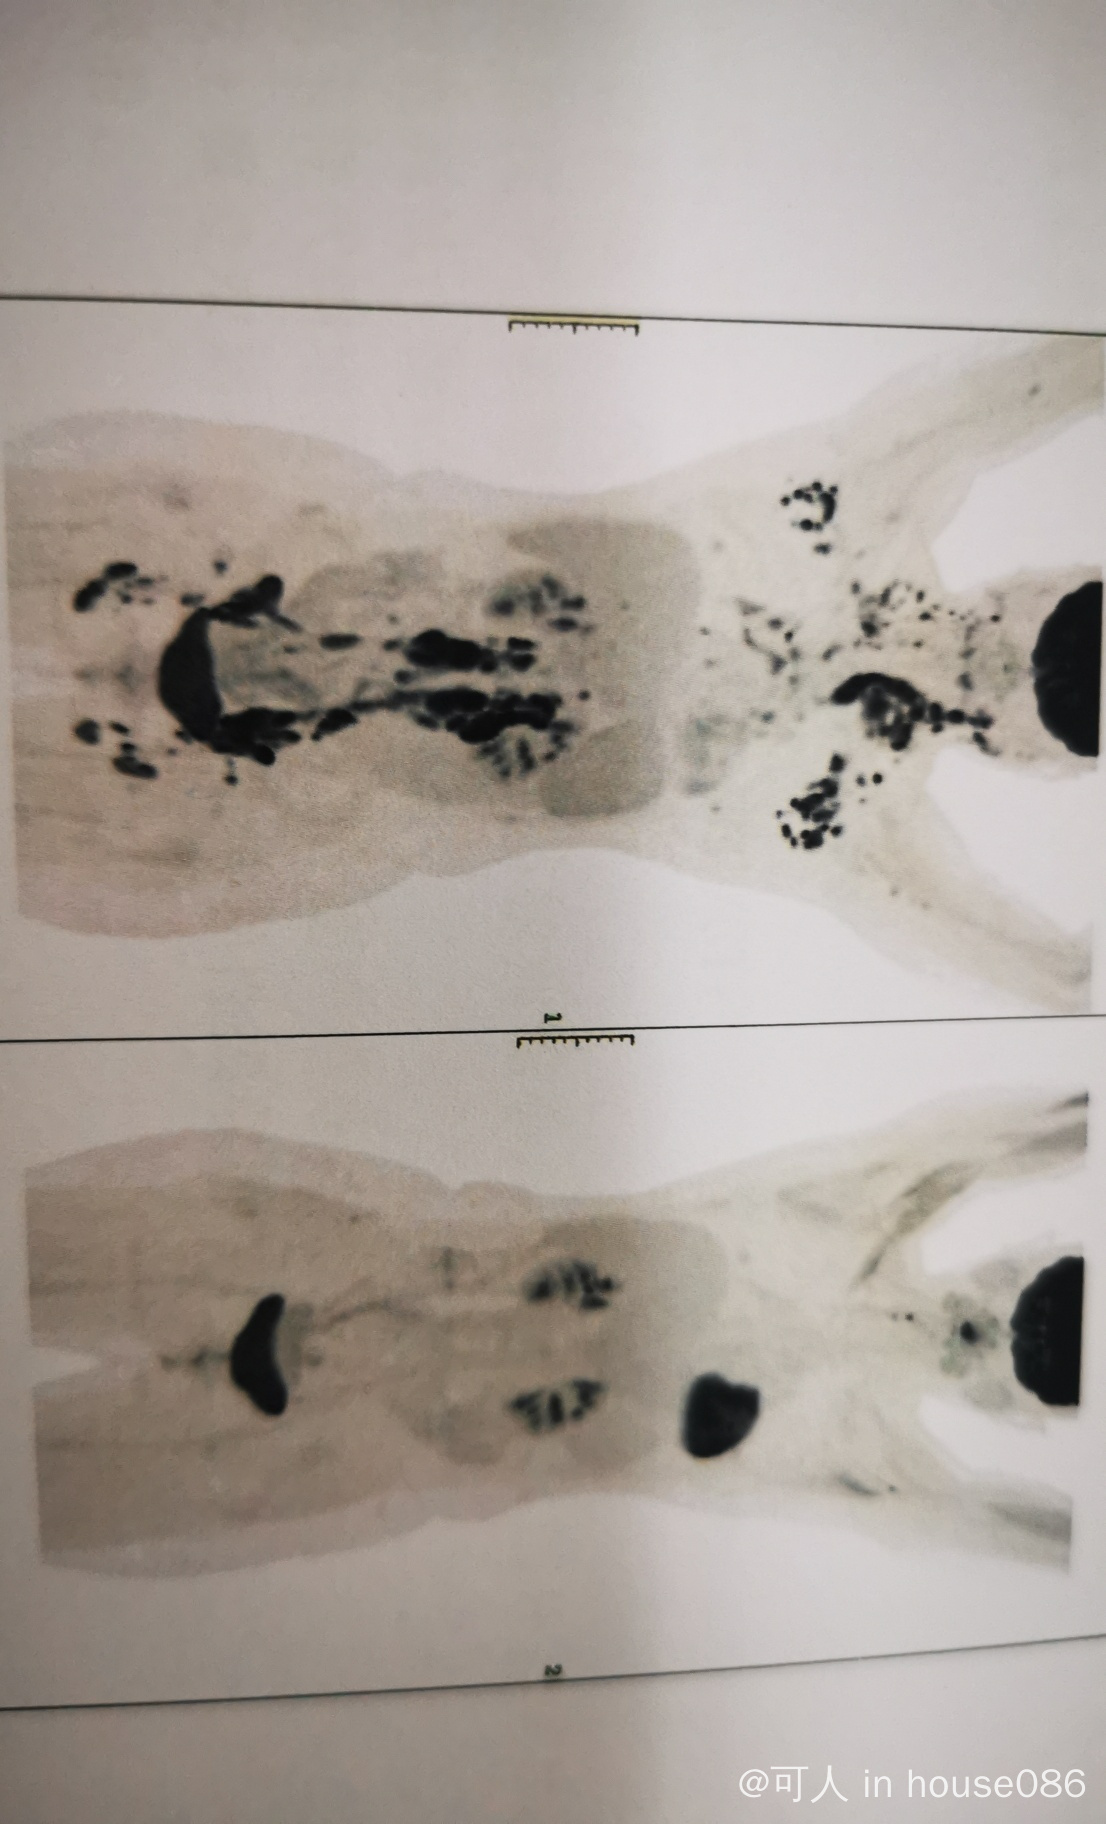

r2,第6次(好消息,达到完全缓解)

今天是第六次过来打r2了,医生告诉我个好消息,根据pet CT的结果,打了5次(二个疗程)后已经达到完全缓解了.啦啦啦。国庆前最后一天,人明显少多了,速度也都提升了,大家都有一种按耐不住要去放假的冲动